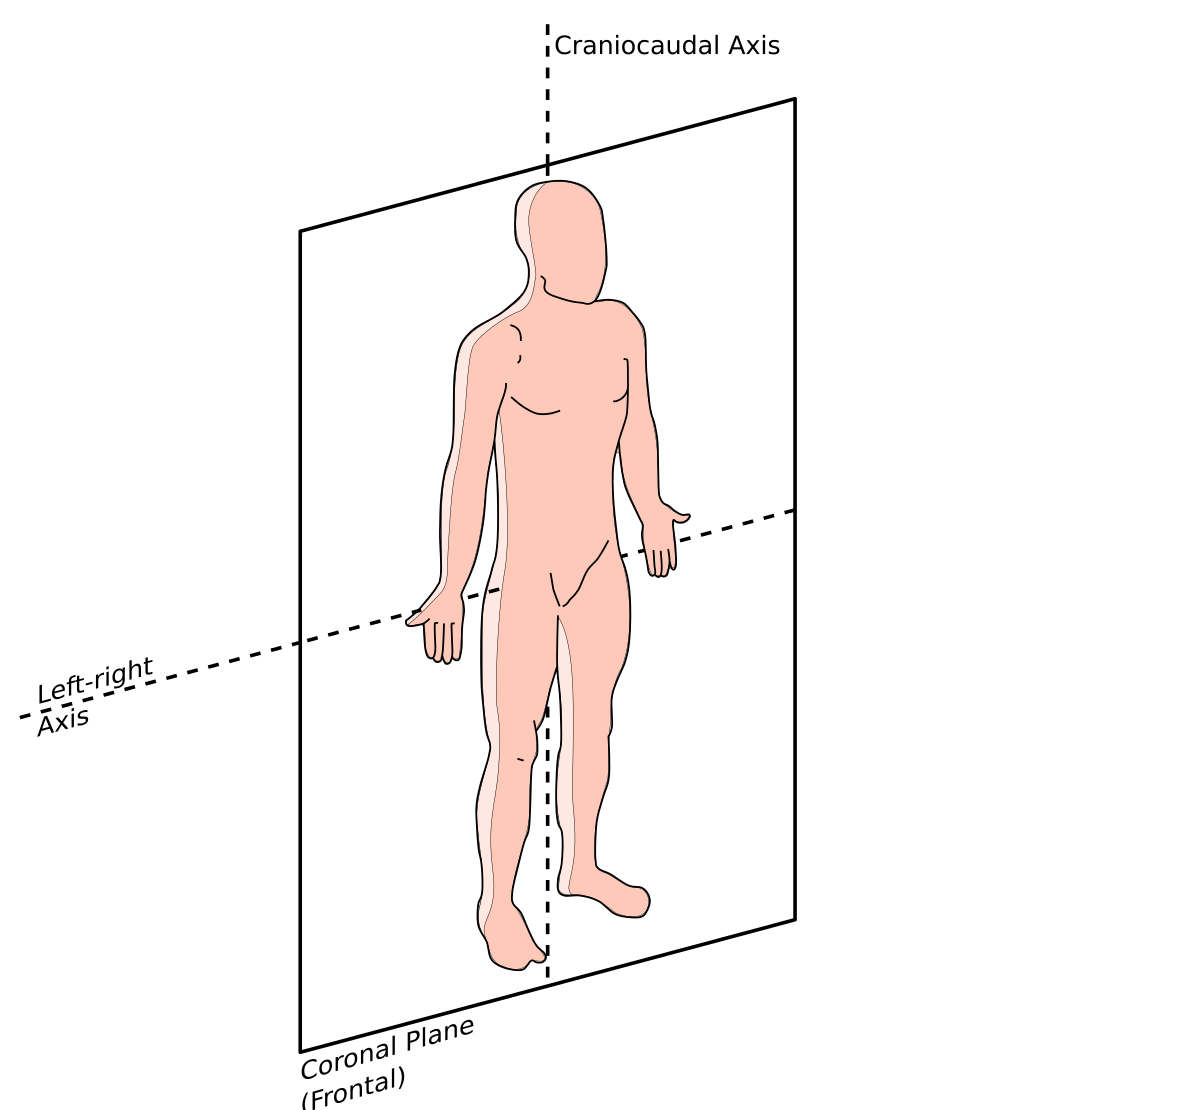

矢状面、冠状面、水平面が分からない? これで完全理解!! 身体の方向をあらわす3つの基準面 矢状面、冠状面、水平面 、本当に理解している?ここって、結構間違えやすい部分だよね。 なので、今回は「矢状面 正中面 」「冠状面」「水平面」のそれぞれの覚え方を。

矢状面、冠状面、水平面が分からない? これで完全理解!! 身体の方向をあらわす3つの基準面 矢状面、冠状面、水平面 、本当に理解している?ここって、結構間違えやすい部分だよね。 なので、今回は「矢状面 正中面 」「冠状面」「水平面」のそれぞれの覚え方を。

人体の基準面で矢状面 と 冠状面 がごっちゃになる人へ。 このイラストのイメージがあると記憶に残ります。

矢状面、冠状面、水平面が分からない? これで完全理解!! 身体の方向をあらわす3つの基準面 矢状面、冠状面、水平面 、本当に理解している?ここって、結構間違えやすい部分だよね。 なので、今回は「矢状面 正中面 」「冠状面」「水平面」のそれぞれの覚え方を。

矢状面、冠状面、水平面が分からない? これで完全理解!! 身体の方向をあらわす3つの基準面 矢状面、冠状面、水平面 、本当に理解している?ここって、結構間違えやすい部分だよね。 なので、今回は「矢状面 正中面 」「冠状面」「水平面」のそれぞれの覚え方を。

horizontal sagittal and coronal planes水平面,矢状面,冠状面 _sigittal coronalhorizontal之间的区别-CSDN博客。

强强的个人技术博客-医学中水平位、冠状位、矢状位这三个位置的概念分别是什么。

分清frontal plane 额状面 、coronal plane 冠状面 、transverse plane 横断面 、sagittalplane 矢状面 -CSDN博客。

关于医学影像中的轴位面 横断面 、冠状面、矢状面的解释_ct轴位和冠状位的区别-CSDN博客。

医学图像的三个主要平面:矢状面、冠状面、横断面_冠状面和矢状面示意图-CSDN博客。